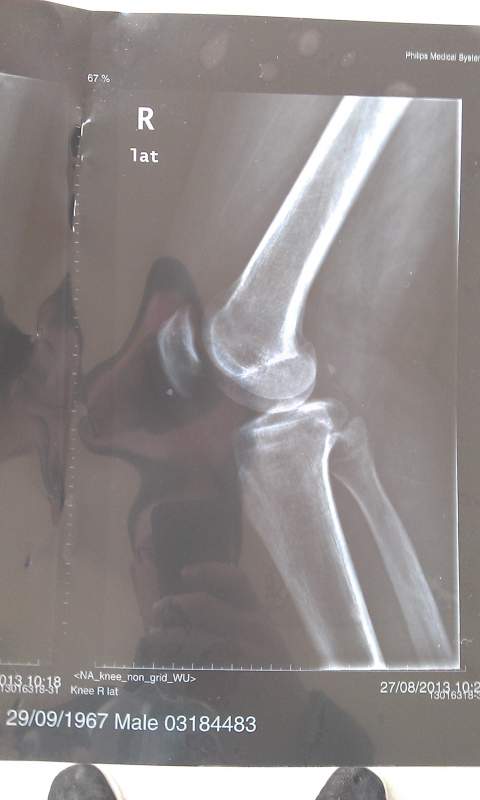

病情描述:膝盖内侧局部区域疼痛,只有那一小块地方,由于不小心崴的一下,已经有近两年时间,求助大神帮忙看下这个X光片,是个什么情况?X光片上规则白点是什么原因?是引起病症的直接原因吗? IMAG0062.jpg IMAG0063.jpg IMAG0064.jpg IMAG0065.jpg |